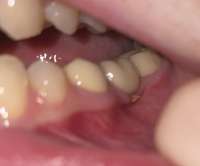

сапыч, пару тройку лет назад вырвали зуб, делал мост, имплант ставить не стал, ща смотрю какая-то хуйня из под моста вылезла, если дергаю, чуть кровоточит, высовывать не стал. че это может быть, кусок недобитого корня? высовывать надо?

IMG4087.jpeg 41Кб, 574x477

574x477

Выглядит как рецессия десны, если не регулярно чистишь зубы мб зубной камень образовался ниже коронки.

Непонятно, что торчит, но кость рассосалась сильно. Надо будет делать наращивание кости и имплант.